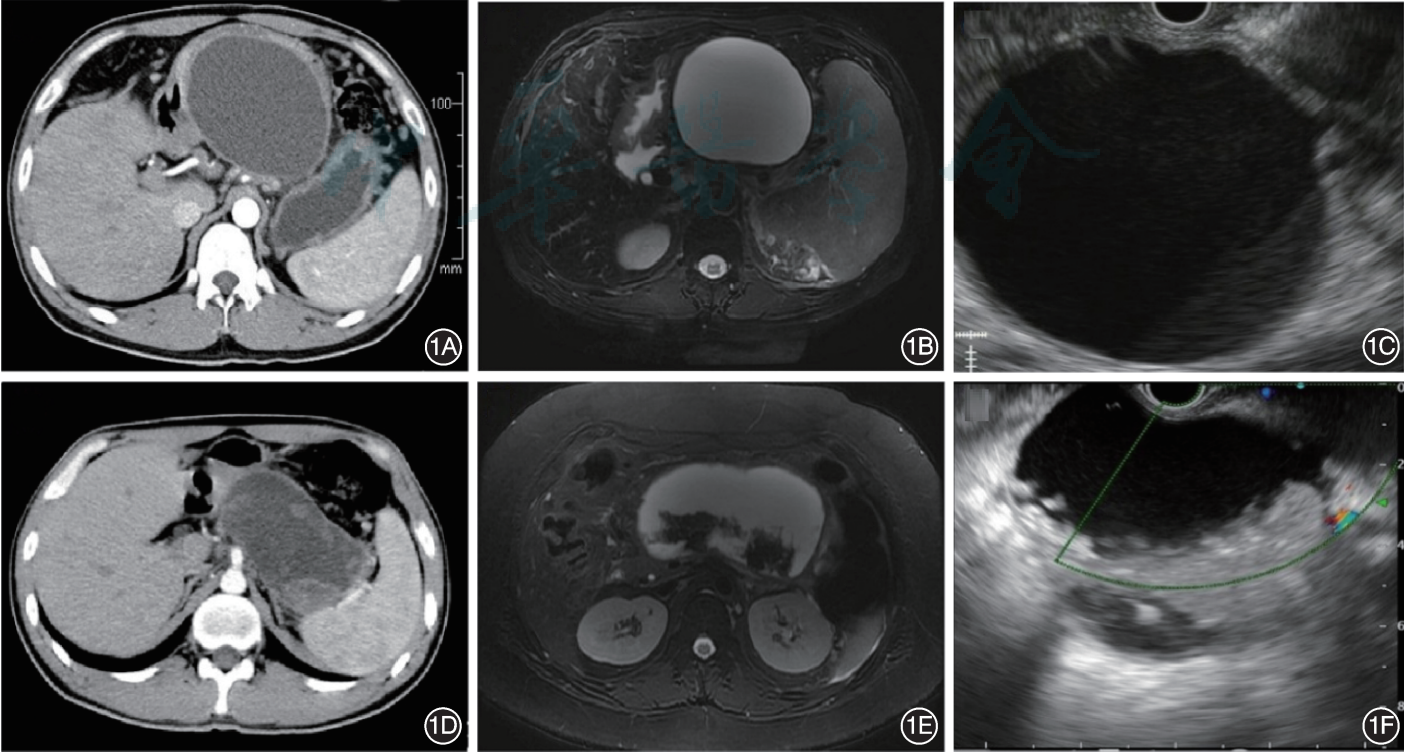

CT或MRI均為診斷PPC和WON的首選影像學檢查方式,MRI更有助于判斷囊腫液體及壞死物含量。

1A:PPC的CT圖像;1B:PPC的MRI圖像;1C:PPC的EUS圖像;1D:WON的CT圖像;1E:WON的MRI圖像;1F:WON的EUS圖像

圖源:中國胰腺假性囊腫內鏡診治專家共識意見(2022年)